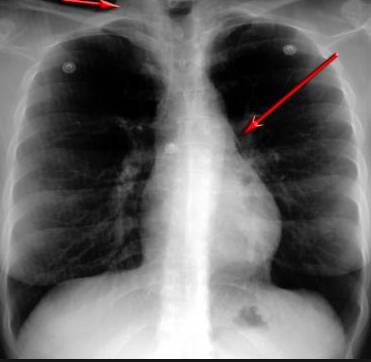

并且,因?yàn)楹粑到y(tǒng)結(jié)構(gòu)復(fù)雜,在體檢時(shí)醫(yī)生很難通過(guò)一種檢測(cè)手段,判定早期患者的病情。

整個(gè)肺部看得清清楚楚!

4D高清透視!

使用這臺(tái)掃描儀,將直接把器官變成3D圖形!細(xì)微的毛細(xì)血管,幾毫米大的肺泡和支氣管,都將能看的一清二楚!

你的每一個(gè)氣泡,每一段支氣管,哪兒有病變都清清楚楚的將展示在醫(yī)生面前!

也就是說(shuō)在一切都還沒(méi)開(kāi)始惡化前,把這些有問(wèn)題的器官組織都暴露的一清二楚:

沒(méi)有這項(xiàng)新技術(shù),醫(yī)生在做體檢的時(shí)候,很難通過(guò)一種測(cè)試斷定一個(gè)人是否有呼吸系統(tǒng)疾病。

可是現(xiàn)在他們不但能看到整個(gè)肺部的3維結(jié)構(gòu)圖。還能看到空氣進(jìn)入人體后的所有微小變動(dòng)!